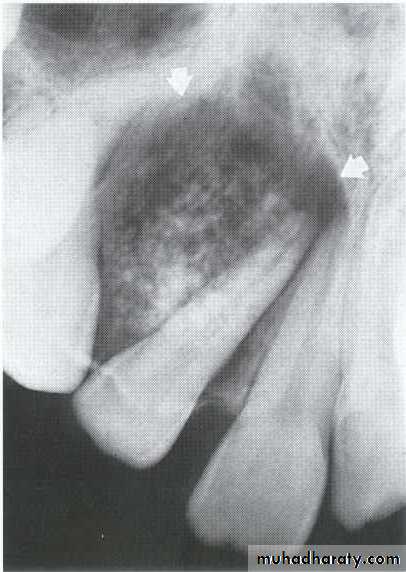

A: Radiolucent apical scar left after successful endodontic treatment..

B:New bone forming from the periphery of theLesion.

If the R.L.enlarged, pain,sinus,or no regression in the size of lesion after 6months (P. A. Cyst).

Apical scar